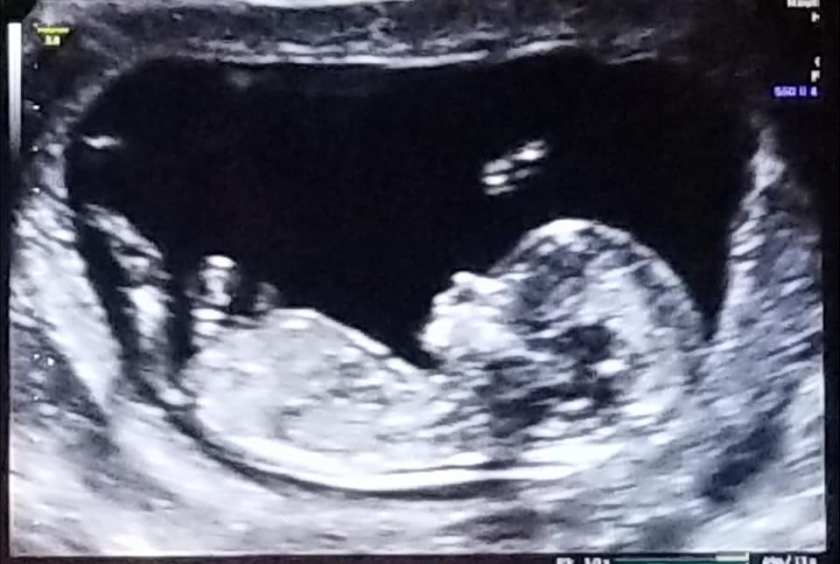

My Mom would have wanted it written that way, though. She believed that each life is precious right from the start... even before birth [and so do I]. She was already excited to meet her newest grandbaby in 2021... we talked about different name suggestions and their meanings;  she was never bashful about telling me which combinations sounded weird or if the potential initials/monogram would spell out an uncouth acronym.

While I stood next to my Mom's bedside early Thursday morning, I leaned over to whisper the name we chose for our little girl. So, yes... "Norah Jane" is ours... and she is named after the most remarkable woman I've ever known... Patty Jane Terry.